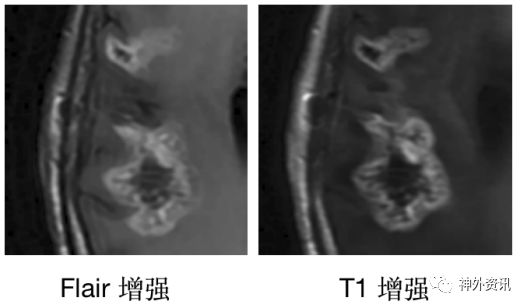

术后9.6个月加做灌注成像和Flair增强(图6)

![]()

图6. 术后9.6个月的磁共振灌注影像和Flair增强,显示增强病灶具有升高的血流量和血容量,Flair增强较T1增强略弱。

鉴于肿瘤血流速度和血容量高于正常,Flair序列增强强度低于T1增强。诊断考虑肿瘤复发。

鉴别间变假性进展与肿瘤复发的单次检查目前首选磁共振灌注成像[4]。但是并非所有医院都有条件做磁共振灌注检查。我们推荐做“液体衰减反转恢复(flair)”序列的增强检测,是一种简便易行的检查。通常肿瘤复发病灶的flair增强低于或等于T1增强的信号,而假性进展病灶的flair增强后信号通常超过T1增强序列[5]。(图7)

图7. 本患者Flair增强和T1增强的对比,可见Flair增强弱于T1增强,提示此病灶为肿瘤复发。